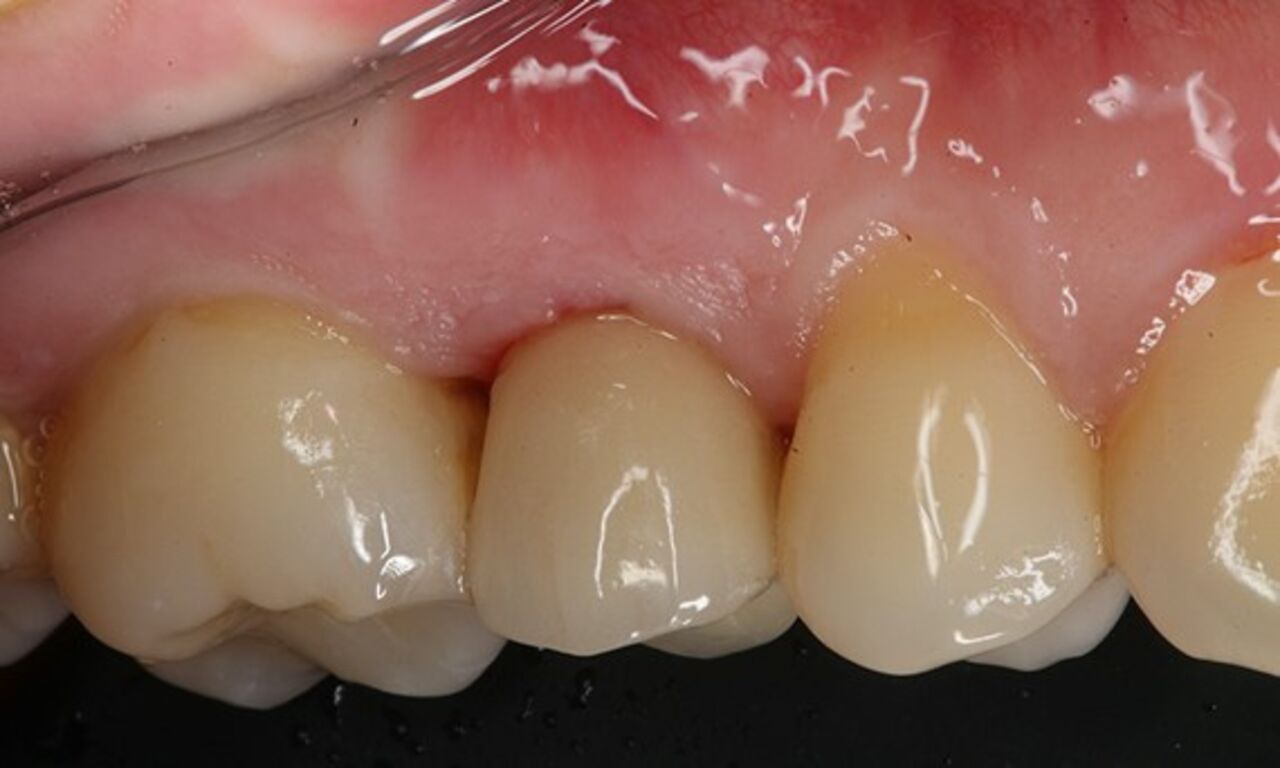

SoftTissue Chamber – größeres Weichgewebevolumen und hohe Ästhetik

Exzellente Ästhetik

Langfristiger marginaler Knochenerhalt für eine exzellente Ästhetik über Jahre hinweg. Sie wissen, dass Sie gewonnen haben, wenn Ihr anspruchsvollster Patient dauerhaft zufrieden ist.